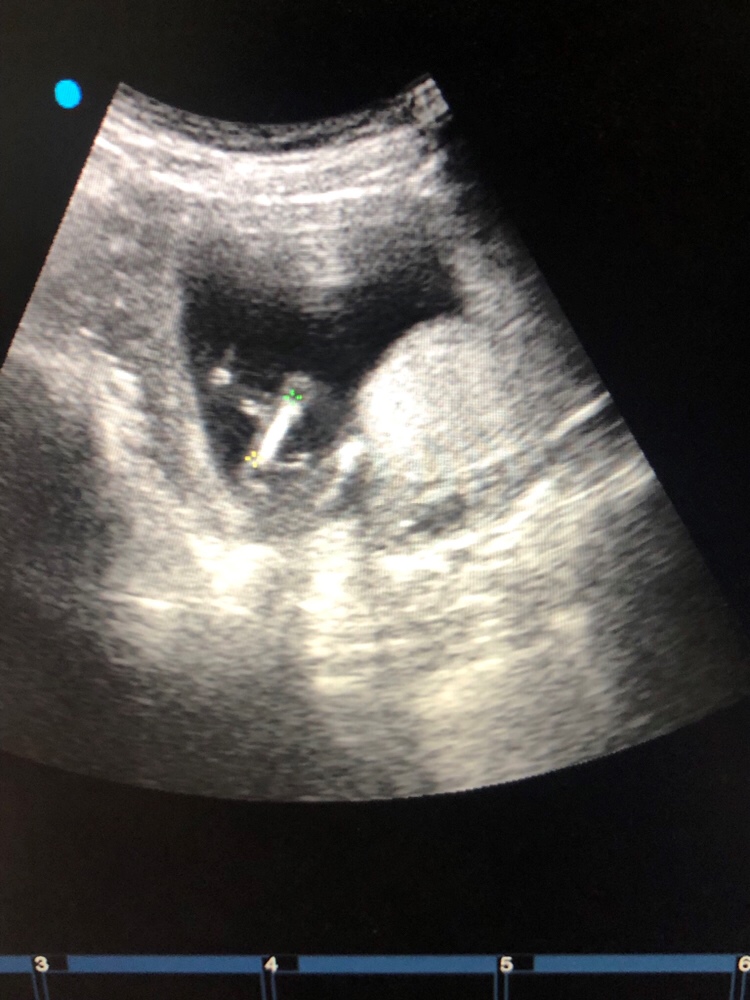

孕10周+6天